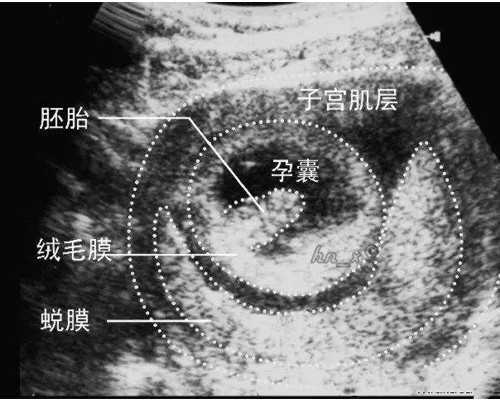

所谓胚胎养囊即囊胚培养就是将受精后第3天的胚胎(D3)在体外继续培养2-3天,囊胚的形成对于胚胎是一个优胜劣汰的过程,只有发育潜力好的胚胎才能形成囊胚。所以养囊不是你想养就能养成,最关键的还是要看胚胎质量。

试管婴儿囊胚培养需要的设备和环境有:控制各种气体容量、温度、光照、酸碱度及相应的序列营养基,让胚胎能够发育成60-200个的细胞。这个阶段的胚胎(取卵后培养5到6天)被称为囊胚。